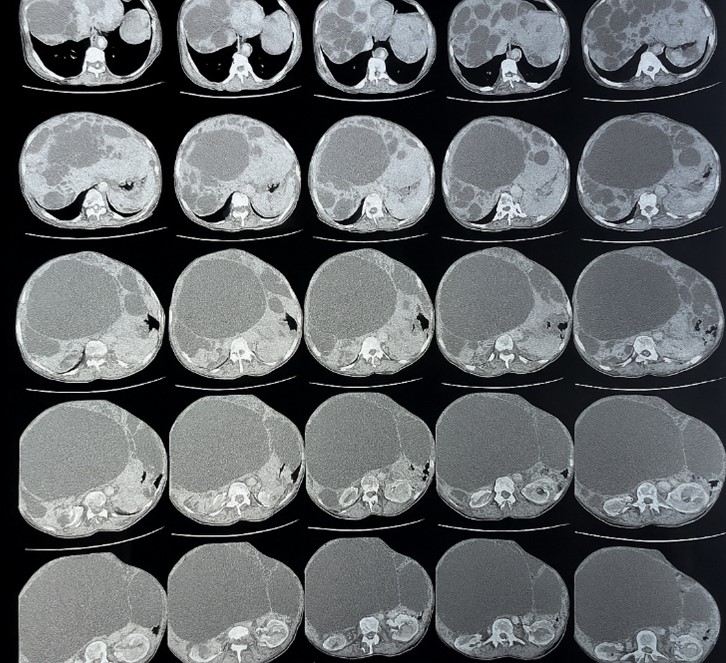

An enlarged liver (measuring 20 cm in craniocaudal height), with irregular contours and homogeneous enhancement after contrast administration. The liver harbored multiple cystic lesions (more than 10), involving all hepatic segments. These lesions were round to oval, fluid-filled, with thin walls, no post-contrast enhancement. Some contained septations, and others showed peripheral calcifications. No communication with the biliary tract was noted.

The largest cyst had an exophytic growth pattern, located in the right lobe of the liver, measuring 211 x 118 mm, with a height of 235 mm.

Figure 2: CT scan image showing multiple hepatic and renal cysts suggesting a Polycystic liver disease.